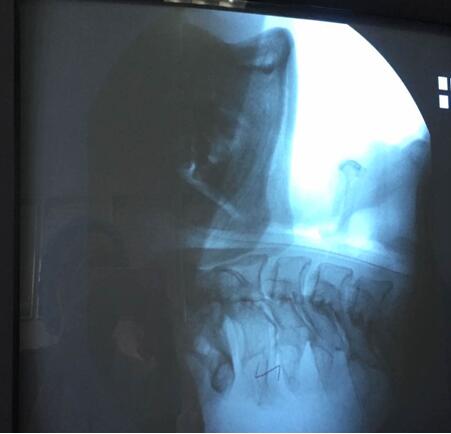

吞咽造影檢查,是在X線透視下,針對口、咽、食管的吞咽運動所進行的特殊造影,此項檢查可以進行點片或錄像來記錄所看到的影響,并加以分析。通過吞咽造影檢查,臨床上可以明確患者是否存在吞咽障礙,可以發現吞咽障礙的結構性或功能性異常的病因及其部位、程度和代償情況,吞咽障礙發生在哪個時期,有無誤吸,尤其是會并發肺炎的高度危險的隱形誤吸,嚴重程度如何,評價代償的影響,為選擇有效治療措施(進食姿態治療和姿勢治療)和觀察治療效果提供依據。因此,吞咽造影檢查被認為是診斷吞咽障礙首選和理想的方法,常被認為是評價吞咽障礙的“金標準”,對指導臨床吞咽治療工作具有重要意義。

該患者于6月23日在山東濰坊因腦干梗死出現吞咽功能減退,并在當地一家醫院進行檢查與治療,之后轉入我院進行診治,經過詳細的資料查詢和反復思索,我院康復醫學科責任總治療師梁莉娜大膽提出開展吞咽造影檢查的設想,隨即與介入導管室積極協調,制定了詳細的實施方案,于7月14日順利完成檢查。最終,初步檢查造影結果為吞咽障礙(咽期)、誤吸、環咽肌不完全開放。